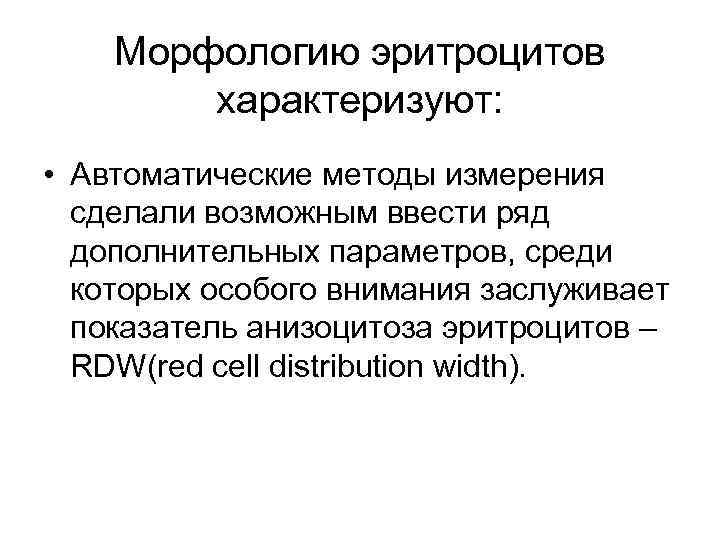

Морфологию эритроцитов характеризуют: • средний объем эритроцита (МСV – mean corpuscular volume), • среднее содержание гемоглобина (МСН - mean corpuscular hemoglobin) • средняя концентрация гемоглобина (МСНС - mean corpuscular hemoglobin concentration).

Морфологию эритроцитов характеризуют: • средний объем эритроцита (МСV – mean corpuscular volume), • среднее содержание гемоглобина (МСН - mean corpuscular hemoglobin) • средняя концентрация гемоглобина (МСНС - mean corpuscular hemoglobin concentration).

Морфологию эритроцитов характеризуют: • Автоматические методы измерения сделали возможным ввести ряд дополнительных параметров, среди которых особого внимания заслуживает показатель анизоцитоза эритроцитов – RDW(red cell distribution width).

Морфологию эритроцитов характеризуют: • Автоматические методы измерения сделали возможным ввести ряд дополнительных параметров, среди которых особого внимания заслуживает показатель анизоцитоза эритроцитов – RDW(red cell distribution width).